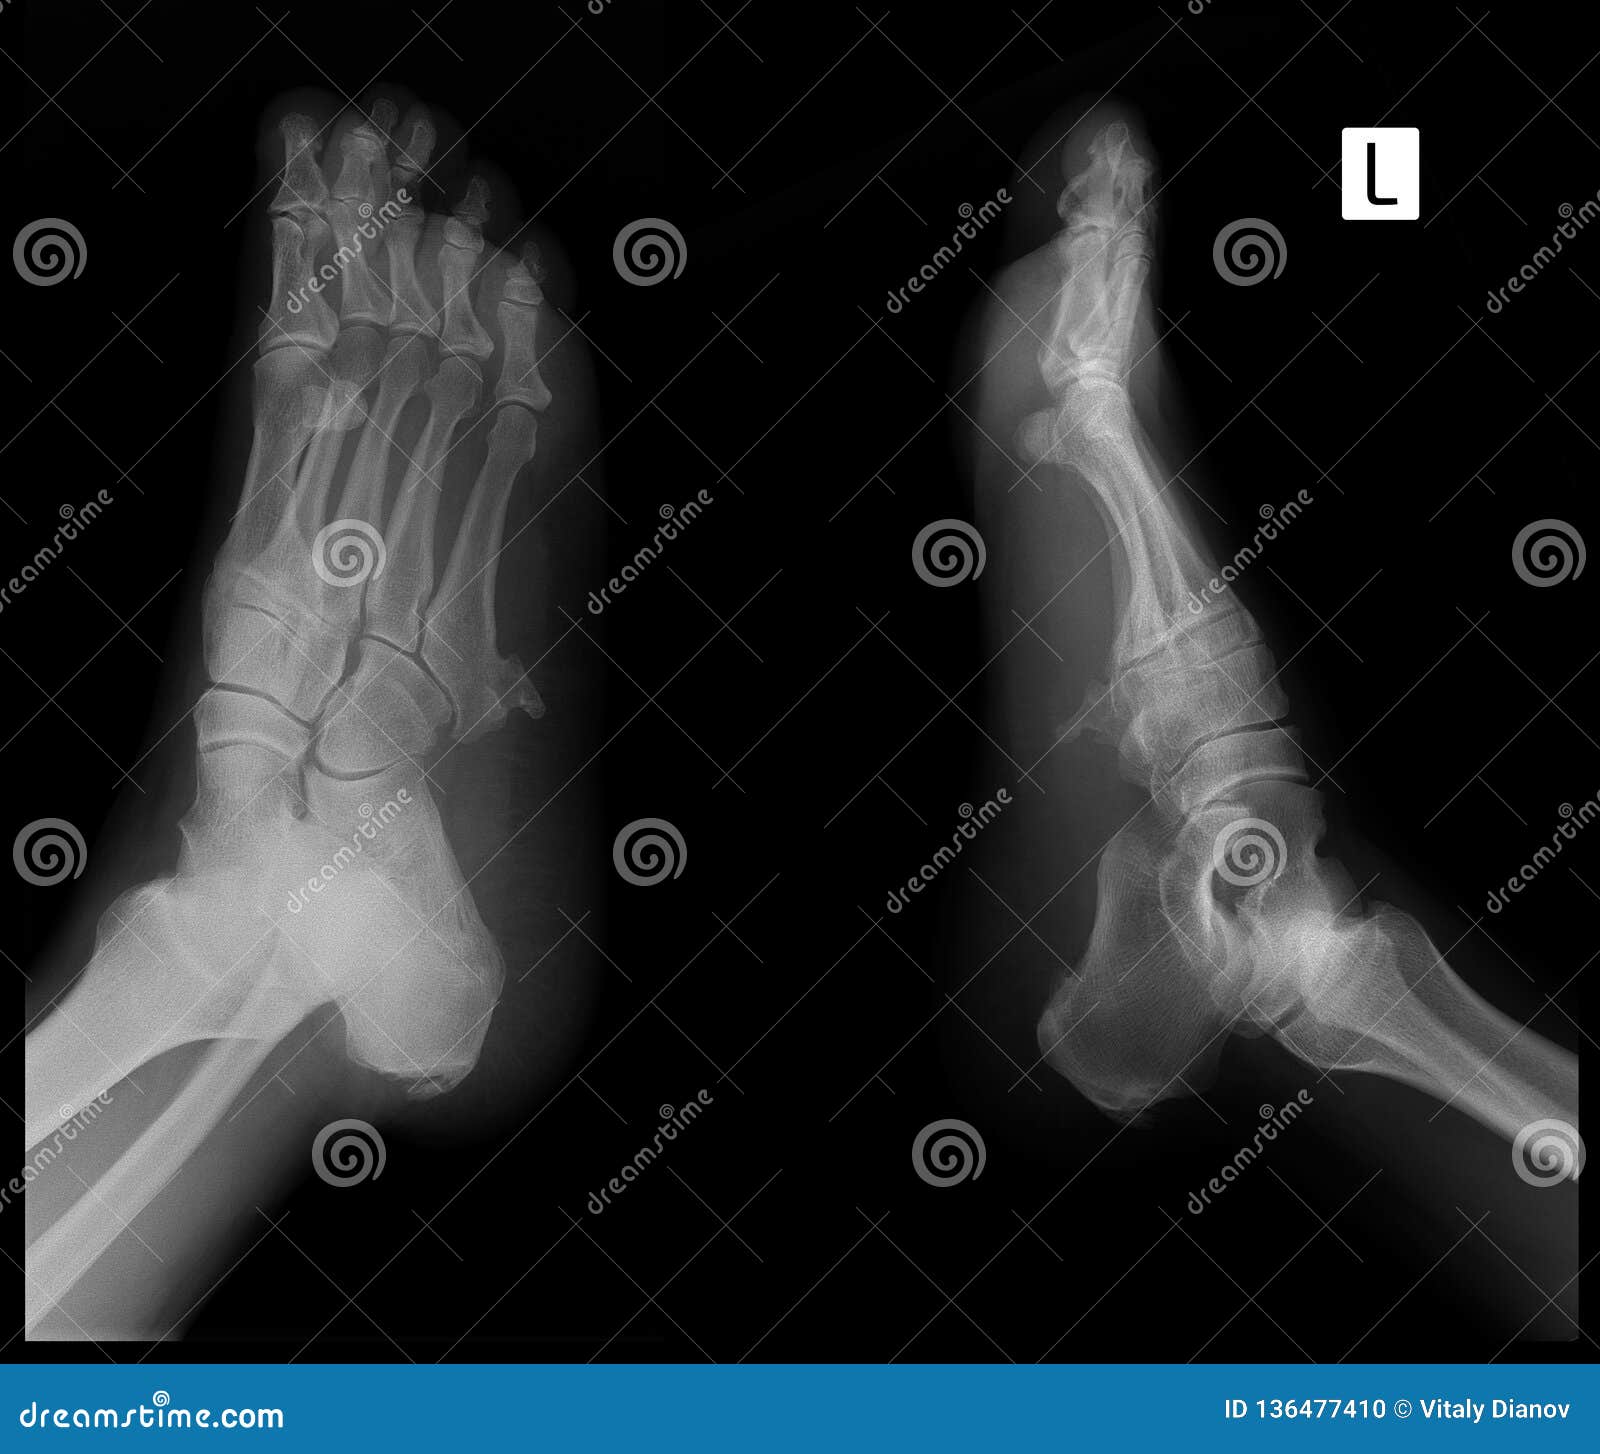

Экзостоз пальцев стопы

Экзостоз пальцев стопы 143 фотографий